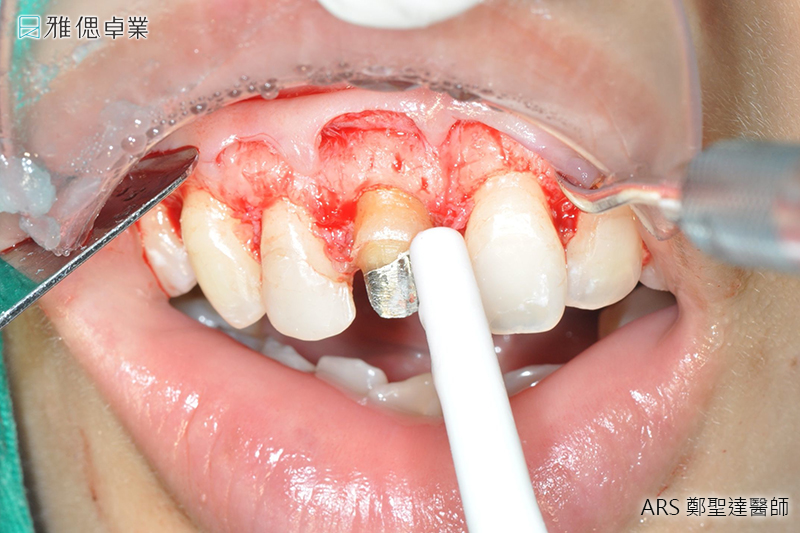

水雷射牙冠增長術

水雷射用來切割組織的水分子是具有生理相容性。也因為 Er, Cr: YSGG 雷射所產生的能量會充分被水吸收,在手術過程中不會產生熱及震動,在大部分的病例中,病患的疼痛感受會大幅的降低,因而能減少對麻醉的需求,同時也能縮短在診療椅上的時間。因為疼痛減輕、並降低出血量,又減少了高速鑽牙時所產生的噪音,解決了許多病患害怕鑽牙及不敢看牙醫的困擾。

- 疼痛感較低, 治療僅局部塗麻

- 絕佳可預測的療效

- 不需擔心牙齦邊緣萎縮

實際案例水雷射牙冠增長術術前術後對照